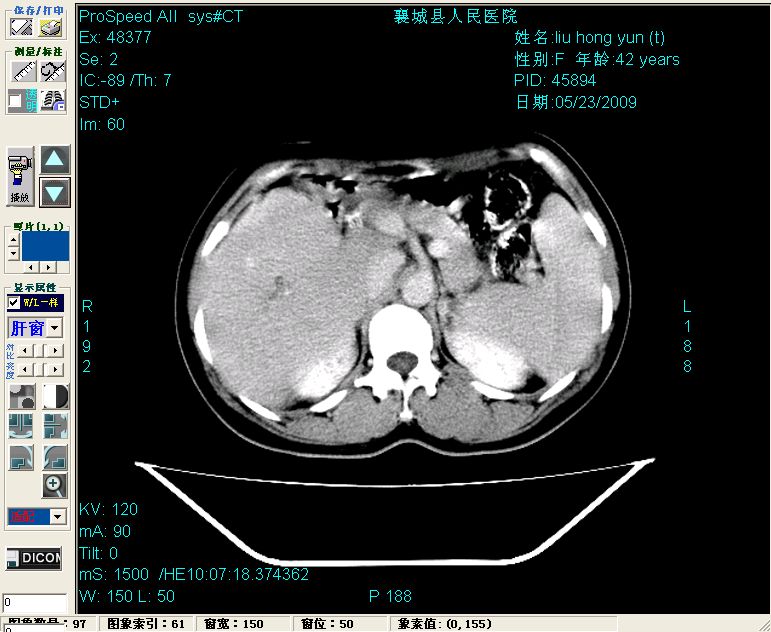

增强:

胰头部见结节状高密度影,其前方略可分辨扩强胆部管,平扫到增强始终有,但现在尚难与胃肠造影剂鉴别.

结合病史考虑,1现在引起黄疸体征的原因应该是胆总管胰段结石阻塞,建议局部胃肠造影剂排空后复查.

胆总管末端结石伴肝内胆管扩张合并结石!另:不除外合并胆系感染!